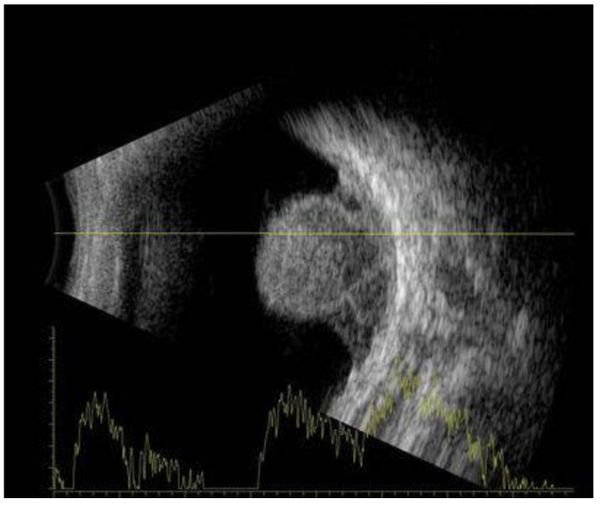

2. Ультразвуковое исследование глазного яблока. Это безопасный метод, позволяющий получить двухмерное изображение всего глаза, на котором можно оценить размеры, форму и общую структуру образования, глубину его проникновения в окружающие ткани и наличие таких осложнений, как кровоизлияние или отслойка сетчатки. Также УЗИ широко используется для динамического наблюдения при органосохраняющем лечении меланомы хориоидеи. Однако у этого метода есть существенное ограничение — очаги толщиной менее 1 мм могут остаться незамеченными [18][19].

![Меланома хориоидеи при УЗИ [1] Меланома хориоидеи при УЗИ [1]](/media/bolezny/melanoma-horioidei/melanoma-horioidei-pri-uzi-1_s.jpeg?dummy=1757506888521)

Меланома хориоидеи при УЗИ [1]